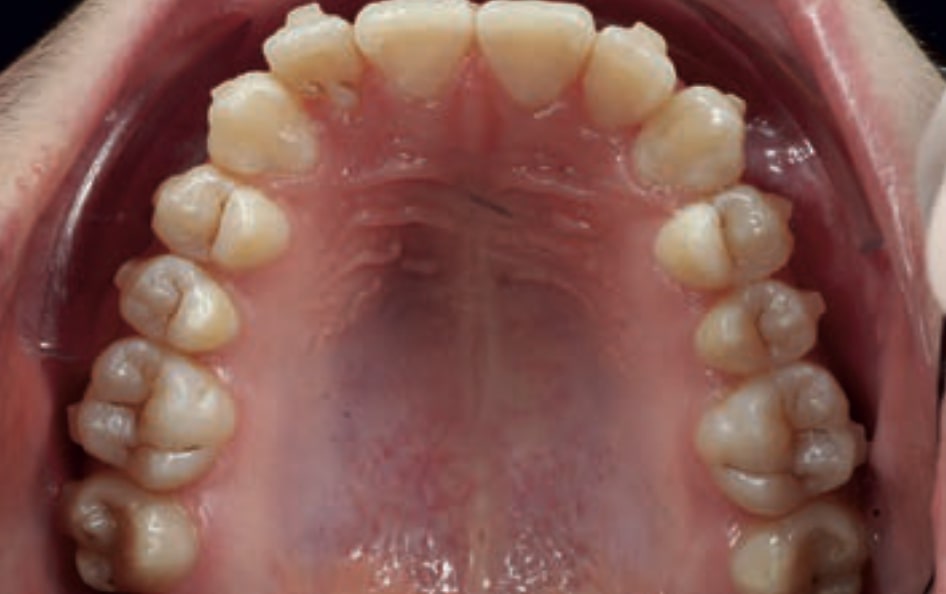

Chief complaint: The patient, a 19-year-old woman, was evaluated to undergo orthodontic treatment using the Angel Aligner Pro system. She presents with a skeletal Class III, mesofacial, with a dental Class III malocclusion and a 2 mm deviation of the lower midline to the left. Teeth 33 and 43 are out of the arch and cortical bone, with a crossbite issue on tooth 33. Fortunately, no functional issues affecting swallowing or breathing have been detected. The patient’s motivation for starting treatment was a general review of her dental and aesthetic health. The soft tissue analysis reveals mandibular protrusion that influences her facial profile. This diagnosis highlights the need for a comprehensive approach to address dental and skeletal misalignments, improving both the patient’s functionality and facial aesthetics.

• Dental Class III, 2 mm deviation of the lower midline to the left. 33 and 43 out of the arch and the cortical bone.

• Crossbite of 33.